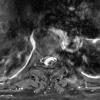

NEOPLASMS (MENINGIOMA)

Transitional (4)